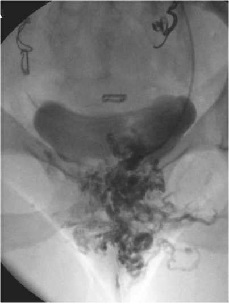

![]() Kamina P, et al. Phlebologie 1989 isolated SCP with Superficial Chronic Venous Insufficiency (SCVI) Grading of PCS?imaging classification in practice → to plan procedure

Imaging classification in practice → to plan the procedure

有人将盆腔静脉淤血按血流速度分为两型

Type I Low-flow pelvic varicocele 低速盆腔静脉曲张

a. Non-cross-pelvic. 非跨越盆腔

b. Cross-pelvic. 跨越盆腔

Type II High-flow pelvic varicocele 高速盆腔静脉曲张

a. Non-cross-pelvic (high-outflow through the ipsilateral hypogastric vein). 非跨越盆腔(通过同侧的髂静脉)

b. Cross-pelvic varicocele 跨越盆腔静脉曲张

1. High-outflow through the contralateral hypogastric vein. 通过对侧髂内静脉的高血流

2. High-outflow through both hypogastric veins. 双侧前内静脉高血流

3. High-outflow through the contralateral ovarian vein. 通过对侧卵巢静脉高血流

4. High-outflow through all of the above veins. 通过以上所有静脉的高血流